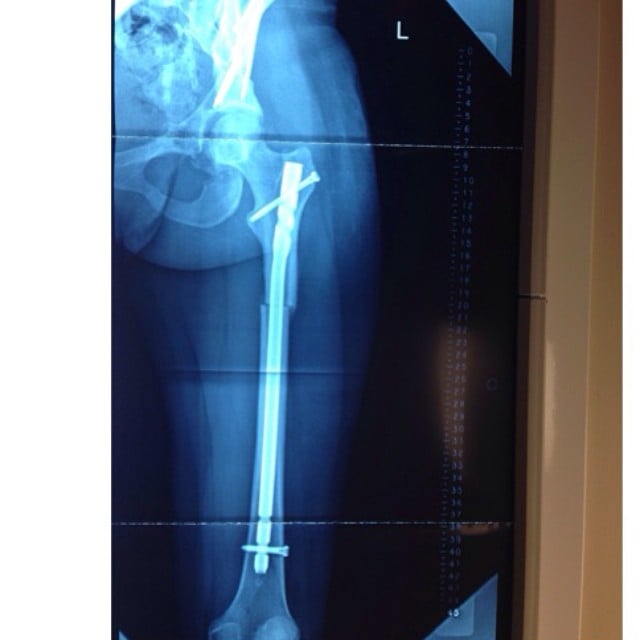

My story is a bit different than most regular surgical stories out there, but one thing is for certain: I made the best decision of my life by going to HSS. The moment my family and I walked in there we knew that the doctors and nurses where going to do everything possible to help change my life. I was born with a condition called Hip Dysplasia, and anteversion as well as patella dislocation and a few other long medical terms that most won't understand so to shorten it up, my left leg was causing me extreme pain in both the hip and knee area due to the fact that my hip bone was incorrectly rotated causing my entire bone structure to twist inward leading to muscle tears, bone deterioration and patella dislocations as well as other painful issues. I spent several years traveling around the United states hearing from one doctor to another that there was nothing they could do for this condition until I reached HSS and came in contact with Dr. Kelly who showed us that there was a light at the end of the tunnel. In 2010 I underwent my first hip surgery to take care of a labral tear as well as a bone spur. I instantly noticed pain relief, but we all knew it was only temporary, so Dr. Kelly brought on a team of doctors to review my case and decide what the best treatment would be which is when I met Dr. Buly who would change my life as we knew it forever! Dr. Buly read over all my scans and x-rays and approached my family with a surgical plan that he felt 100% confident with. That surgery was called Periacetabular Osteotomy Femoral osteotomy (derotational) in which with the help from Dr. Helfet, he was going to break my femoral bone and hip bone changing the actual structure and placing a metal rod into my femur and a bunch of screws to hold my hip and femur in place. I remember feeling my heart stop when I heard what was going to happen but I knew he was the best of the best and even though this is one of the rarest surgeries out there I was in good hands, so the date was scheduled. I under went my second operation on Feb. 5th 2014 and about 9 hours later I woke up to Dr. Buly holding my hand telling me everything had gone great and I knew than I had a better life a head of me. My recovery was extremely hard and took a very long time but every minute of it was worth it. I had to relearn how to walk and all, but i remember the moment I saw my leg, I cried and not because of the incisions and pain but because for the first time my leg looked "normal" and there was the possibility for the first time to live a full and adventurous life that I had always dreamed of. I did have to undergo 6 months out a third surgery to remove all the hardware due to the fact my body was rejecting it but Dr. Buly had warned me that could happen but after a few more hours I was awake and ready to get back to PT. I am now one year from when I first started this long surgery recovery with Buly and I can tell you that if I was asked if I would ever do it again I would 100% say yes. Even through all the hard times and the pain it was completely worth it! Dr. Buly and the HSS nurses have forever changed my life and I could never thank them enough. He has given me my life back and the chance to do everything and anything I want to that never was possible before. I am 23 years young and ready to conquer whatever life throws at me!!! I used to always say I wish but I can't because of my leg but now if someone asks me do you want to go to the gym or any other activity I can say yes for the first time and it feels amazing. I will always hold Dr. Buly and all the other team members dear to my heart for giving me the life I never thought would be possible, so thank you from the bottom of my heart Dr. Buly and HSS staff! So if you are in need of any type of surgery I would not think twice about going to HSS, I can promise you that you will not be disappointed.